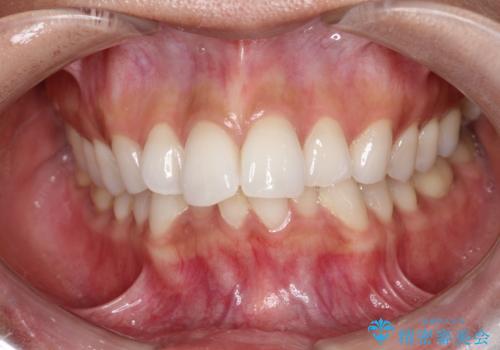

前歯の突出と下顎の偏位を改善。審美ワイヤーで整えるバランスの良い歯並び

閉院による転院からのリカバリー。インビザラインからワイヤー矯正への切り替え

担当医 河口智英